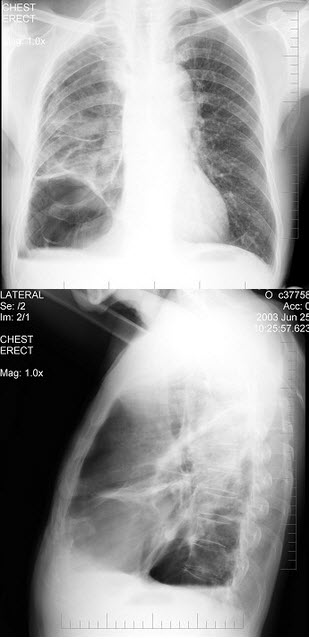

264、单项选择题

男,65岁,呼吸困难伴胸闷,胸片结果如图,最可能的诊断为()

A.气胸

B.肺结核

C.慢性阻塞性肺疾病

D.肺部感染

E.支气管扩张

284、单项选择题

患者48岁,男性,常感胸闷气逼,近1个月渐加重,X线检查见图。最合适的诊断是()

A.右侧气胸

B.右侧肺大疱

C.两肺肺大疱

D.正常胸片

E.肺气肿